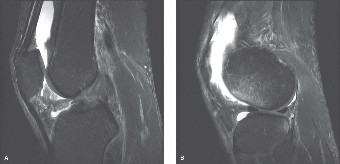

CASE 5 A 24-year-old graduate student twists her knee while walking in high he…